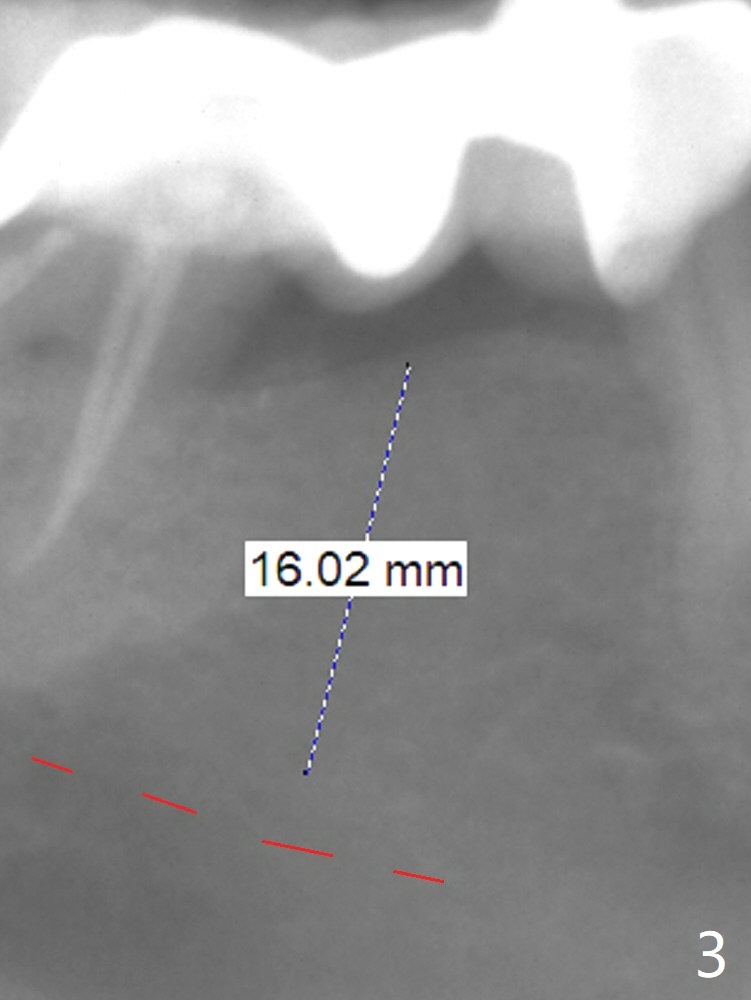

A 60-year-old man has food impaction under the pontic of the lower right FPD (Fig.1-3: #30). The ridge should be thin, since the bone density in the edentulous area is low. The mesiodistal width is also limited. A 1- or 2-piece implant (3.5x8.5 mm, Fig.4 (CT coronal section)) is expected. Use wheel to section the ridge vertically and Rongeur to remove the ridge. Grind the latter for graft. Place a wide abutment to increase the width of the pontic site to reduce food trap.